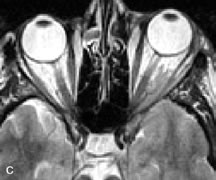

PATIENT PREPARATION Before MRI is performed, patients must be screened and prepared to avoid the potential hazards associated with the strong magnetic field. Patients who have ferrous aneurysm clips or cardiac pacemakers, who depend on life-support equipment, or who retain a possible metallic intraocular foreign body are not candidates for this imaging modality. MRI cannot be performed on obese patients who cannot fit into the bore of the magnet. Patients who are claustrophobic may not tolerate a prolonged period of study within the confines of the magnet, whereas others might do well if given a mild sedative. All worn metallic objects (e.g., necklaces, watches) should be taken off, credit cards set aside, and eye makeup removed before entering the room containing the magnet.5,20,34,35,36 NORMAL ORBITAL ANATOMY T1-weighted images provide the best anatomic details of the orbit because they display superior contrast resolution between normal structures (see Fig. 8). The vitreous has a long T1, resulting in an intermediate signal similar to brain, whereas the crystalline lens and sclera appear dark because of a longer T1 and short T2. The extraocular muscles, like all skeletal muscles, demonstrate a moderately long T1 and short T2 and highly contrast with the intense signal of the surrounding orbital fat (adipose tissue has an extremely short T1). The lacrimal glands appear as mottled areas of reduced intensity of the signal from the orbital fat in the lacrimal fossa. The optic nerves are seen with the same signal intensity as brain white matter and are hypointense relative to the orbital fat because their Tl is longer than the Tl of fat but shorter than the Tl of water. Cortical bone is not well delineated because it contains little free water, yielding minimal signal in MRI, and thus appears dark on all pulse sequences. This feature explains why MR images of the orbital apex and intracanalicular portion of the optic nerves are superior to comparable CT scans. Partial volume averaging of the bones in these regions obscures soft tissue details on CT images, whereas MRI reveals the signals only from the soft tissue structures with no cortical bone input. Bone marrow, on the other hand, is seen as a relatively intense signal because of its high fat content (see Fig. 8).37,38 T2-weighted pulse sequences are not ideal for imaging normal anatomy; however, they are particularly useful in revealing pathologic conditions (see Fig. 9). T2-weighted studies are most easily recognized by a bright vitreous signal. ORBITAL DISEASES Vascular Lesions Cavernous hemangiomas appear as well-circumscribed, smooth, usually intraconal masses that are isointense to muscle on T1-weighted images and hyperintense on T2-weighted images (Fig. 12). Patchy early enhancement is typically followed by diffuse, more homogeneous enhancement.39 The internal architecture of the mass, including septation and internal vasculature, may often be appreciated with high-quality orbital imaging.40 Lymphangiomas consist of ectatic vascular channels within a connective tissue stoma with varying degrees of lymphoid cellularity. On MRI, these tumors are typically poorly circumscribed, multicompartmental, and heterogeneous, often showing cystic dilations with fluid levels (Fig. 13). The signal characteristics within lymphangiomas vary considerably, reflecting cystic and solid components and the varying paramagnetic characteristics of blood at different stages of degradation.40–42 Acute hemorrhage appears hypointense on both T1- and T2-weighted formats. Methemoglobin present in subacute hemorrhage (3 to 14 days) leads to hyperintense signal on both T1- and T2-weighted images.41 A small percentage of lymphangiomas appear radiologically indistinct from orbital cavernous hemangiomas.43 Orbital varices are venous malformations that expand with increased systemic venous pressure, such as with Valsalva maneuvers. Because rapid acquisition of images during a Valsalva maneuver is important in imaging such a lesion, conventional or spiral CT is currently the modality of choice.44 MRI is an excellent modality for demonstrating enlargement of the cavernous sinus and dilation of the superior ophthalmic vein in patients with high-flow carotid-cavernous fistulas (Fig. 14).37MRA may be helpful in the evaluation of the venous outflow pattern. The rapidly flowing blood in these vascular structures carries the excited protons out of the section before they can be imaged, resulting in their dark appearance.5 In low-flow dural arteriovenous malformations, MRA may help define the arterial feeding vessels.45 Neural Lesions MRI is more effective than CT in delineating the intracranial optic nerves, chiasm, and optic tracts and, for this reason, is the preferred imaging modality in the evaluation of optic nerve disorders. The spatial relationships and image contrast of the orbital tissues with intraorbital optic nerve tumors is comparable between the two imaging modalities. The normal nerve is isointense to brain and appears enlarged and kinked owing to infiltration of an optic nerve glioma on T1-weighted images. Gliomas appear hyperintense on T2-weighted images and may be heterogeneous owing to cystic areas within the tumor. Contrast enhancement is variable.46 Intraorbital and intracranial optic nerve sheath meningiomas are usually isointense to cortical gray matter on Tl-weighted images and remain isointense on proton density studies (Fig. 15). Gd-DTPA is useful in delineating the intracranial extension of optic nerve meningiomas.7,47 The hyperostosis of bone and calcification associated with meningiomas are not demonstrated as well on MRI studies as on CT scans.20,37 Gd-DTPA–enhanced MRI also appears promising in the study of the permeability of the blood–brain barrier in selected optic neuropathies.22,48 MRI may reveal an enlarged optic nerve and some degree of contrast enhancement in cases of optic neuritis.49 Muscle Disorders Extraocular muscle enlargement in patients with thyroid-associated orbitopathy is demonstrated equally well with CT and MRI studies. However, the superior tissue contrast on MR images reveals better details of the relationships of the optic nerve to the thickened muscles at the orbital apex (Fig. 16).50 In addition, MRI may be able to differentiate between muscles that are enlarged as a result of edema and active inflammation and those enlarged because of fibrosis by their T2 relaxation times.21 Quantitative MRI was not found to be accurate in predicting the success of low-dose orbital irradiation.51 However, a muscular index relating the diameters of the rectus muscles to the bony orbital dimensions was useful in predicting optic nerve compression.52 MRI is also effective in imaging orbital tumors of mesenchymal origin, such as rhabdomyosarcoma, particularly in the assessment of extension into the anterior and middle cranial fossae (Fig. 17).37 The lack of any pathognomonic radiologic features necessitates rapid orbital biopsy when rhabdomyosarcoma is suspected. Osseous Lesions In general, CT is the imaging modality of choice when details of quantity and quality of bone are needed; however, abnormalities of bones can be detected indirectly by MRI. Cortical bone appears black (signal void) on MR images because of its low proton density and free-water content. The absence or discontinuity of the signal void of the orbital walls may represent bony destruction or fracture. Hyperostosis associated with prostate metastases or meningioma is visualized as areas of black smudging.50,53 Diseases in which the bone is replaced by pathologic tissues with a high free-water content, such as fibrous dysplasia, are well demonstrated on MRI. An intermediate signal intensity on T1-weighted images and hypointense signal on T2-weighted images is representative of fibrous dysplasia. Enhancement on post–Gd-DTPA MR scans is seen and is more evident in areas that are less mineralized.54 Cystic Lesions Dermoid cysts appear as rounded, well-defined lesions typically contiguous with an orbital bony suture. The high-intensity signal on T1-weighted images is attributed to the sebaceous-produced lipid contents (Fig. 18).31,50 Mucoceles may demonstrate a hypointense or hyperintense signal on MR images, depending on the concentration of proteinaceous or inflammatory fluid components. The integrity of the bony walls of the expanded sinus cavities cannot be assessed on MR as well as by CT.37,50,55,56 A high-signal intensity on Tl- and T2-weighted images is characteristic of orbital chronic hematic cysts because of the blood-breakdown products within the cysts.57 Trauma Although soft tissue relationships are usually better demonstrated on MRI, the evaluation of craniofacial bony trauma is preferable with CT. For example, prolapse of orbital fat through a fracture site and hemorrhage of adjacent tissues are demonstrated in an MR image, but the actual fractured bone is not imaged. Three-dimensional MRI of the orbit in subacute trauma has been described,58 although its precise role is not currently established. MRI has been suggested to be superior to CT in detecting intraorbital wooden foreign bodies.59,60 In a series of penetrating orbital injuries with organic foreign bodies, however, MRI was able to identify the foreign body in only four of seven cases.61 With an in vitro model for wood foreign body, McGuckin and colleagues concluded that CT was the imaging modality of choice.62 A careful history and, in selected cases, plain films to rule out a metallic foreign body are crucial before MRI is considered in patients with periocular trauma. MRI is particularly helpful in the detection and characterization of subperiosteal hematomas of the orbit (Fig. 19). They are most commonly seen in the subperiosteal space of the superior orbit as well-defined masses following a traumatic injury. The signal intensity varies depending on the acute, subacute, or chronic nature of the hematoma, based on the stage of blood degradation. Fresh hemorrhages are hypointense on T1-weighted images and hyperintense on T2 images. Hematomas that are 1 to 7 days old are hypointense on both T1- and T2-weighted images. T1-weighted images of hematomas more than a week old are hyperintense due to the oxidation of deoxyhemoglobin to methemoglobin, whereas the T2 images remain hypointense.63 Metastatic Tumors Breast carcinoma metastatic to the orbit has been demonstrated to be hypointense to the surrounding orbital fat on T1-weighted studies and hyperintense on T2-weighted images and has an affinity to the extraocular muscles (Fig. 20).50,64 The MRI characteristics of prostate carcinoma metastatic to the orbit have been described as involving the greater and lesser wing of the sphenoid, orbital roof, and optic canal. Diffuse bone hypertrophy with isointense or slightly hyperintense tissue on T1-weighted images represents the osteoblastic carcinomatous bone infiltration. Contrast enhancement is variable on T1-weighted and fat-suppressed images.65 Most other metastatic tumors also have a lower intensity signal on T1-weighted images and appear to displace or infiltrate normal orbital structures; however, their signal characteristics are variable on T2-weighted MR images.66 Many metastatic tumors demonstrate bright contrast enhancement with Gd-DTPA. Infectious Disorders MRI findings of preseptal and orbital cellulitis typically include increased signal intensities on T2-weighted images of the eyelids and orbital fat, respectively, due to the increased water content of the tissues. Since most cases of bacterial orbital cellulitis are associated with paranasal sinusitis, hyperintense signals of the affected sinuses may also be found on T2-weighted images as well as enhancement of polyps and granulation tissue on postgadolinium T1-weighted MR images. Subperiosteal abscess formation may occur due to contiguous spread of infection from the paranasal sinuses and appear on MRI as an area of intermediate signal on T1-weighted and proton-weighted MR images. The abscess may appear slightly hyperintense compared with muscle on T2-weighted scans with the necrotic contents having the greatest intensity.67 MRI and MRV are more sensitive than CT in revealing cavernous sinus thrombosis. Engorgement of the cavernous sinus, extraocular muscles, and ophthalmic veins is seen with hyperintensity of the thrombosed sinuses evident on all pulse sequences. The enlarged, thrombosed superior ophthalmic vein appears less hypointense than the normal contralateral ophthalmic vein, and hyperintensity within the lumen of the vessel may be seen on T1- and T2-weighted MR images.68 Inflammatory and Lymphoproliferative Lesions Inflammatory conditions of the orbit, both idiopathic (inflammatory pseudotumor) and those of known causes, have been found to be hypointense to fat and isointense to muscle on Tl-weighted studies and isointense or slightly hyperintense to fat on T2-weighted images (Fig. 21).50,64,69 The more fibrous or sclerosing varieties have less signal intensity on T2-weighted images. Marked enhancement is seen in pseudotumor infiltrates after gadolinium administration.70 The same signal characteristics are demonstrated in patients with Tolosa-Hunt syndrome, with mass lesions seen in the cavernous sinuses and orbital apices.71 Lymphomas have MRI characteristics similar to those of inflammatory lesions in that they are hypointense to fat and isointense to muscle on T1-weighted images (Fig. 22). They may appear hyperintense to fat on T2-weighted images, perhaps owing to less fibrosis than that seen in orbital inflammatory pseudotumor, although this is not a consistent finding.31,50,66 Lymphoid tumors typically enhance moderately after contrast injection. Unfortunately, studies have shown that tumor density and homogeneity are similar between inflammatory and malignant orbital infiltrates, and MRI cannot differentiate these lesions.72,73 Lacrimal Gland Tumors Lacrimal gland lesions present special problems in diagnosis and management. Pleomorphic adenoma (benign mixed tumor) should not be biopsied, but rather excised in toto. On the other hand, for lymphoma and inflammatory infiltrates, incisional biopsy is more appropriate than complete excision of the lacrimal gland. Thus, preoperative clinical and radiologic evaluation are especially crucial in planning appropriate surgical management. Pleomorphic adenomas demonstrate long T1 and T2 signal characteristics. They may show heterogeneity on T2-weighted images74 and moderate to marked enhancement with contrast.75 Signal characteristics of adenoid cystic carcinoma include hypointensity to fat on T1-weighted images, hyperintensity to fat with increased T2 weighting, and isointensity to fat on proton density-weighted studies (Fig. 23).31,75 Secondary bony alterations of the lacrimal fossa associated with lacrimal gland tumors, such as remodeling (benign mixed tumor) or destruction (adenoid cystic carcinoma), are seen indirectly on MR images; however, bone windows on CT scans provide better delineation of these changes. In contrast to the round or globular appearance of benign or malignant epithelial tumors of the lacrimal gland, lymphoproliferative tumors usually appear to be molding or draping onto the globe and the surrounding bony orbit. LACRIMAL DRAINAGE SYSTEM DISORDERS MRI with surface coils provides excellent spatial resolution and tissue-specific signal intensities of the lacrimal drainage system. These parameters have been found useful to more accurately demonstrate the extent of lesions in the lacrimal sac and differentiate long-standing mucoceles from solid tumors than CT.76 Physiologic studies in patients with tearing disorders now include MR dacryocystography, in which Gd-DTPA is either placed topically in the conjunctival fornix or injected by cannulation into the lacrimal sac. They provide a detailed morphologic and functional analysis of the lacrimal excretory system; however, they are no more sensitive than digital-subtraction dacryocystography or CT dacryocystography.77–79 INTRAOCULAR TUMORS On MRI, uveal melanomas have a typical appearance that helps to differentiate them from other primary and secondary intraocular tumors as well as choroidal detachments. Pigmented melanomas are hyperintense on Tl-weighted images, hypointense on T2-weighted studies, and hyperintense on proton density–weighted examinations (Fig. 24).30,31,50,80–82 These signal characteristics have been attributed to the paramagnetic properties of melanin because of stable free radicals that shorten the T1 and T2 relaxation times. Moderate enhancement is seen on postgadolinium T2-weighted images. Gadolinium-enhanced T1-weighted images are particularly sensitive in detecting choroidal melanomas.83 MRI may be less sensitive in detecting extrascleral extension of tumor than echography performed by an experienced ultrasonographer.84 Tumors metastatic to the choroid are hyperintense on T1- and T2-weighted images.24 The signal characteristics, however, may be similar to those seen with choroidal melanoma. Choroidal hemangiomas, on the other hand, have an intermediate signal on T1-weighted sequences and become hyperintense on T2-weighted images50 as well as proton density–weighted images.81 Retinoblastomas display moderate signal intensity on T1-weighted studies and a low signal on T2-weighted images.31,80,85 Calcification can be easily detected by CT and ocular ultrasonography but is not imaged by MRI.25,50 The presence of optic nerve involvement is best evaluated by MRI. ACQUIRED ANOPHTHALMIA When an eye is removed owing to tumor or trauma, an implant is typically placed in the intraconal space. MRI may be useful in defining the size, shape, and position of such orbital implants.86 Porous hydroxyapatite or polyethylene implants are preferred by many surgeons performing enucleation or evisceration. A porous implant offers the possibility of supporting a motility coupling peg to increase the movement of the overlying prosthesis. MRI with contrast is used by some surgeons to evaluate the degree of fibrovascular ingrowth in hydroxyapatite87 and porous polyethylene88 implants prior to motility peg placement. |